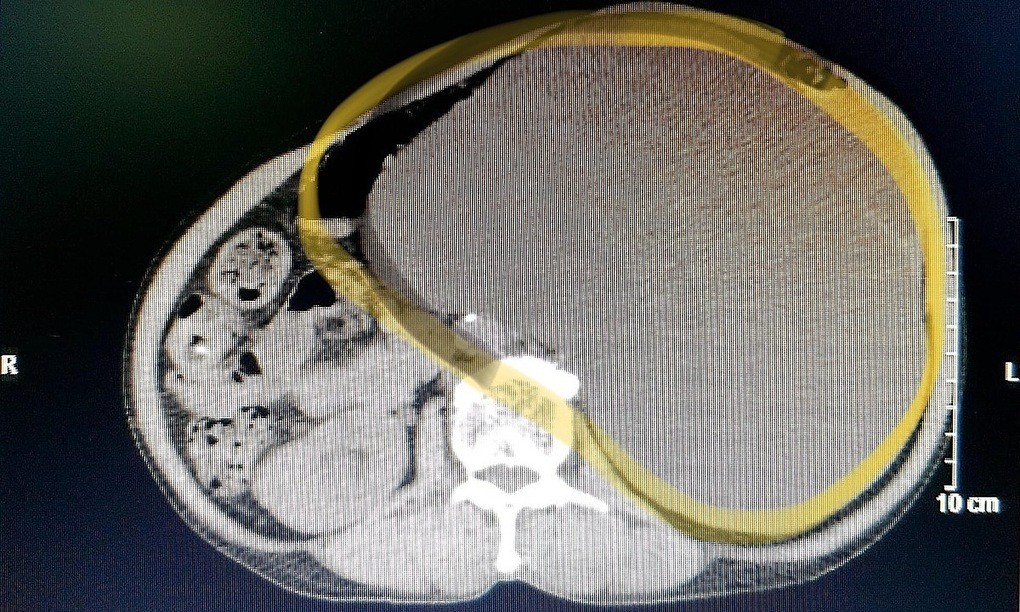

Phim chụp X-quang cho thấy kích cỡ thận trái giãn to. Ảnh: Long Nhật.

QUẢNG BÌNH - Sỏi gây bít tắc, khiến thận của người phụ nữ 71 tuổi ứ nước giãn to độ 4, mất chức năng.

Kích thước bình thường của một quả thận ở người trưởng thành là 12 x 6 cm và không chứa nước tiểu. Song quả thận của bệnh nhân được cắt ra kích thước to gấp đôi, chiếm gần như toàn bộ vùng bụng bên trái. Bác sĩ cũng hút ra gần 4,5 lít nước tiểu đang ứ đọng trong quả thận.